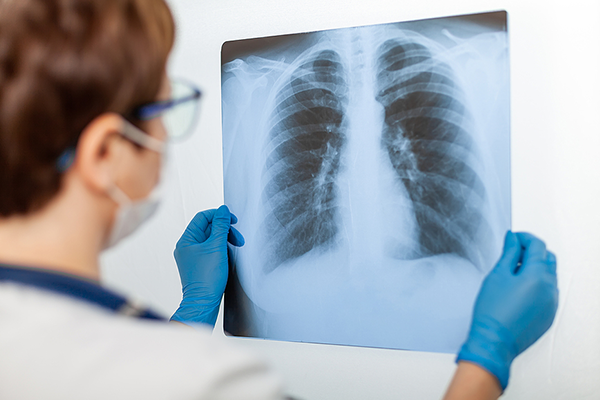

रेडियोग्राफीलाई एक्सरे वा विकिरण पनि भन्ने गरिन्छ । आधुनिक चिकित्सा प्रणालीमा यसले ठूलो महत्व राख्दछ ।

विलहेल्म रोईन्टेनले सन् १८९५ मा आजकै दिन रेडियोग्राफीको अविष्कार गरेका हुन् । रेडियोग्राफीलाई सामान्यतया हामी एक्स-रे अथवा विकिरण भनेर बुझ्दछौं र आधूनिक सरल चिकित्सा प्रणालीमा यसको ठूलो महत्व छ । धेरैजनाले रेडियोग्राफीलाई आफ्नो जीवनको लक्ष्य अथवा करियरका रुपमा लिएको पाइन्छ । हामी अस्पताल जाँदा हाम्रो एक्स रे गर्ने रेडियोग्राफर देखि हाम्रो एक्स-रे को रिपोर्ट बनाउने डाक्टर, एम आर आई, सिटी स्क्यान, अल्ट्रासाउन्ड, इकोकार्डियोग्राफी र एनजिओग्राफीजस्ता अत्याधूनीक एक्स-रे उपकरणहरु सञ्चालन गर्ने प्राविधिकहरु यस प्रविधिको उदाहरणीय सारथी बनि सक्रिय छन् ।

एक्स-रे ले हाम्रो शरीर भित्रका हड्डिहरु, क्याभिटिहरु र कुनै बाहिरी पदार्थ भए नभएको कुरा पत्ता लगाउँदछ । फ्लोरोस्कोपीको माध्यमबाट पाचन प्रणालीभित्रका अङ्गहरुको तस्बिर खिचेर जाँच्न मिल्दछ भने एक आर आई ले हाम्रो शरीरका तन्तुहरुको 2D र 3D नक्शानै तयार गर्दछ । त्यस्तै एनजिओग्राफीका माध्यमबाट रक्तनलीहरुको सम्बन्धमा जानकारी दिनुकासाथै तिनीहरुमा सहज रक्तसञ्चार भए-नभएको कुरा पत्ता लाग्दछ ।

पहिले पहिले डार्करुमको अध्याँरोमा धुलाइने एक्स -रे हरु अब डिजिटल रुपमा सम्प्रेशण हुन थालेका छन्, स्वास्थ्य उपचारमा रेडियोग्राफिको महत्व र भूमिका बढ्दै गएको छ तथापि यससम्बन्धि आवश्यक थप चेतना बढाउनुपर्छ ।